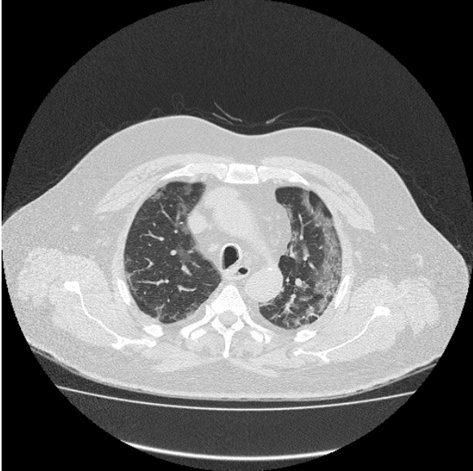

The image reflects the Covid pulmonary consolidation which tends to be patchy or segmental and nodular. It reflects the sensitive stage of the patient, especially when around 10-12 days have passed. Initially, the appearance of GGO reflects early stage of COVID, but as it develops, it continues increasing pulmonary consolidation and air bronchogram in lungs. (Figure 3)

Figure 3 CT image reflecting COVID pulmonary consolidation.

The above image also reflects the presence of ground-glass opacity along with air bronchogram which increases difficulty of breathing to the patient. This stage reflects the presence of pulmonary consolidation in patient’s lungs, which may proceed if immediate treatment is not provided to the patient. The increase in this consolidation means difficulty in breathing, which also show some symptoms like fever, fatigue, and severe cough. (Figure 4)

Figure 4 CT Imaging reflecting presence of Air Bronchogram.